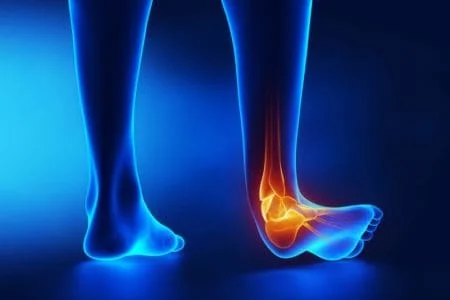

Ankle Sprain

Ankle Fracture

Ankle Syndesmosis Ligament Injury

Ankle Dislocation

Ankle Instability